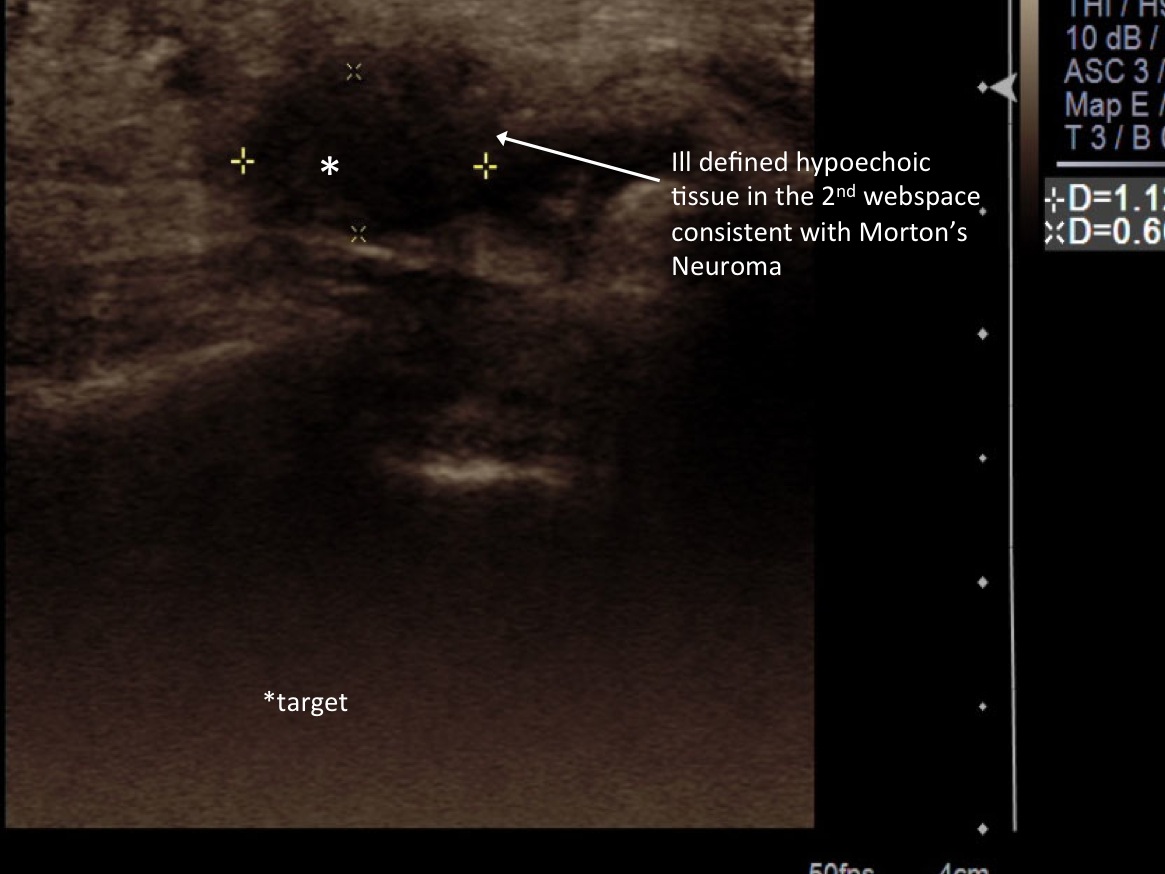

3. Pre-procedure scanning looking from either plantar or dorsal looking for Morton’s neuroma in the webspaces. Place probe in long axis along the distal metatarsals. If well visualized from the dorsal aspect, prefer to place ultrasound probe in that position. Sometimes, it is preferred to have the patient dorsiflex and have the probe plantar, particularly when the patient has subluxations of the MTP joints.

8. Once numb, under ultrasound guidance, advance needle into the neuroma.

9.Test inject with 1% lidocaine. If flow easily exchange for 3cc syringe with injectable steroid (kenalog 40mg/cc) and ropivacaine. Inject approximately 3/4cc into neuroma.